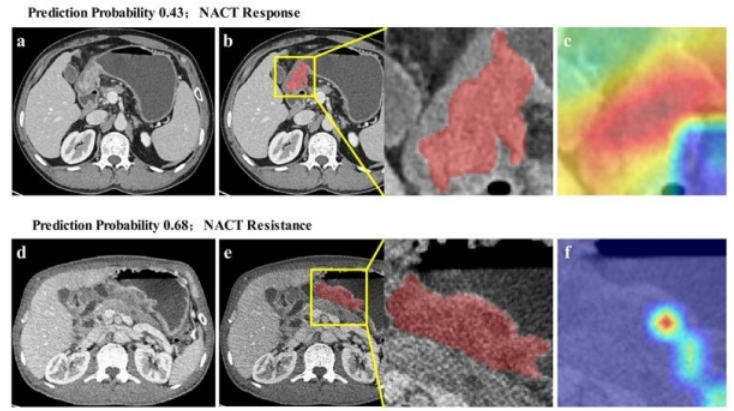

圖2 進展期胃癌新輔助化療療效預測模型可視化圖例

結果表明,所構建的模型精度高且泛化性強,在內外部測試集上預測精度均大于0.75,是目前報道中性能最佳的端到端式進展期胃癌新輔助化療療效預測模型。此外,為了進一步直觀展現模型的可解釋性,團隊通過可視化方法量化腫瘤影像與化療抵抗間的對應關系。腫瘤內部模型激活區域并不均勻,為揭示腫瘤異質性與化療抵抗間的隱含關聯提供了借鑒思路(圖2)。